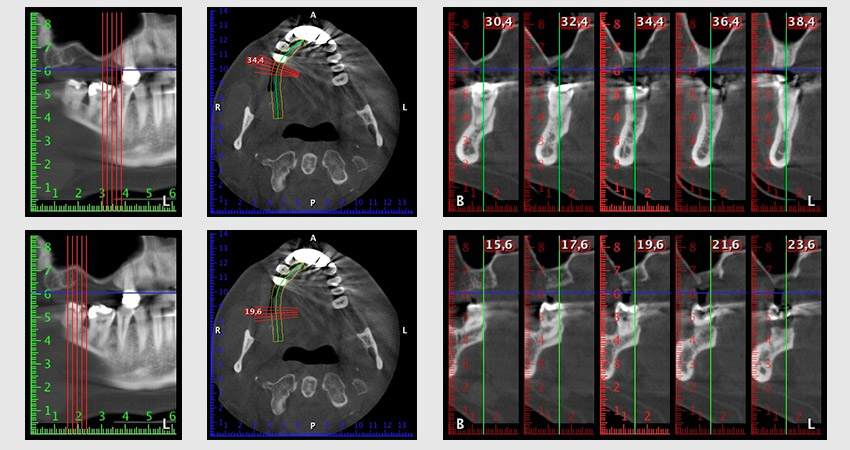

About six months after teeth 16 and 14 were extracted, a digital volume tomography (DVT, Planmeca) examination was performed for planning and risk minimization purposes. It clearly showed that the bone had not regenerated to the desired volume (Fig. 2 to 7).

Image 2 to 7: DVT with greatly reduced horizontal bone volume.

To restrict the augmentation to region 14, and in consultation with the patient, it was planned that implant 16 would be placed, inclined, in the dorso-cranial direction (Fig. 8).

Image 8: DVT with plan of insertion angle for implant 16